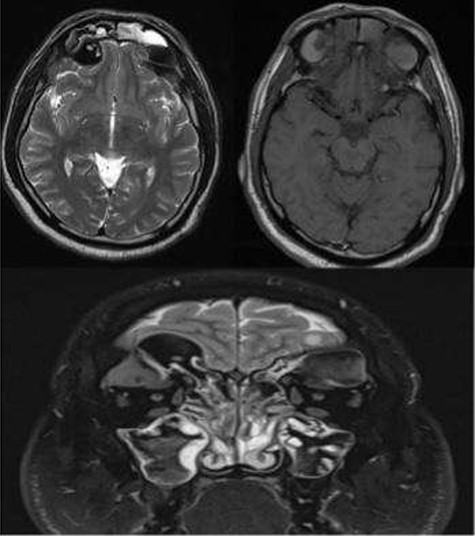

A 35-year-old Saudi male presented to our ENT Clinic with a 1-year history of progressive facial pain, headache, bilateral proptosis, anosmia and nasal obstruction. His past medical history was insignificant. Sinonasal endoscopy revealed multiple bilateral grade IV polyps, occluding the nasal cavities bilaterally. Computed tomography (CT) of the paranasal sinuses showed expansion and remodeling of the frontal sinuses bilaterally (Fig. 1). It is associated with bony dehiscence posterior wall and floor of the sinuses that results in intracranial and intra-orbital extension, respectively. The ethmoid air cells show complete opacification bilaterally with lateral bowing of the lamina papyracea. This along with the frontal sinus orbital extension lead to the clinical presentation of the orbital proptosis. The maxillary antra disease results in remodeling of the stomatal complex and obliteration of the superior two-thirds of the nasal cavities. The contents of the sinuses show mixed iso and hyperdense material. Magnetic resonance imaging (MRI) of the paranasal sinuses demonstrates the orbital and intracranial extension of the disease with no invasion of the adjacent tissues or brain parenchyma (Fig. 2). The hyperdense contents show marked low signal intensity on T2 and high signal intensity on T1.

CT paranasal sinuses axial (a, b) and coronal (c) show sinus expansion, bony remodeling and dehiscence with intra-orbital and intracranial extension. Bilateral orbital proptosis.

MRI paranasal sinuses axial and coronal T2 and axial T1 The MRI shows the expansion with the remodeling of the sinuses and intra-orbital/intracranial extension. The hyperdense contents show marked low signal intensity on T2 and high T1 signal. No tissue invasion of the orbital or brain parenchyma.